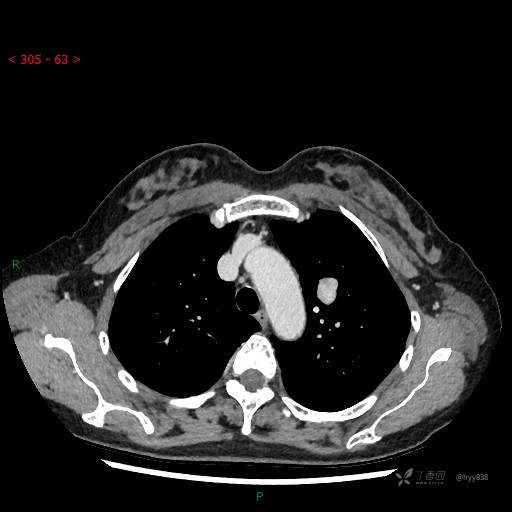

增强静脉期